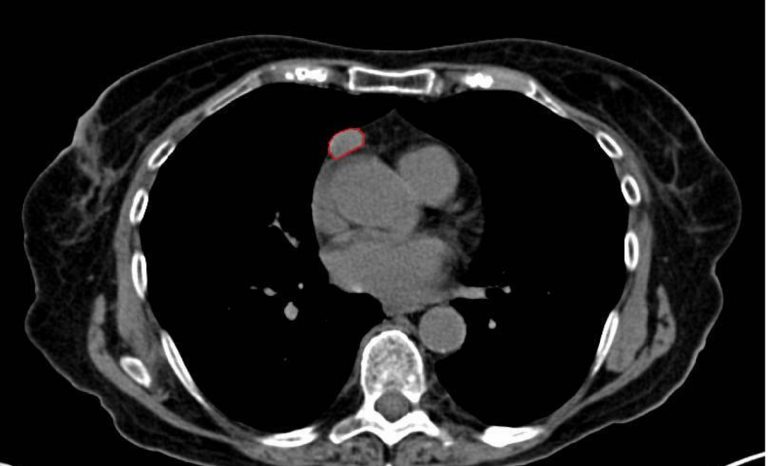

I timomi sono neoplasie che crescono lentamente e originano dalle cellule del timo, una ghiandola situata nella sezione anteriore del mediastino, cioè nello spazio toracico tra i polmoni, collocata dietro lo sterno e davanti al cuore, e che è fondamentale per la produzione delle cellule del sistema immunitario durante l’infanzia. Dopo la pubertà, il timo solitamente diminuisce di dimensioni, ma in alcuni casi può dar luogo a tumori denominati timomi. Tali tumori sono di frequente legati alla miastenia gravis, una patologia autoimmune che provoca sintomi neuromuscolari, quali stanchezza, problemi visivi e difficoltà nella deglutizione. Anche se rari, i timomi hanno un notevole impatto clinico. Oltre al rischio di sviluppo oncologico, possono scatenare disturbi autoimmuni gravi. Una diagnosi precoce e un trattamento adeguato possono migliorare in maniera molto evidente le prospettive di guarigione, rendendo fondamentale discuterne e sensibilizzare sia i medici che i pazienti. Il Gruppo San Donato ha approfondito l’argomento con la professoressa Giulia Veronesi, responsabile dell’Unità Operativa di Chirurgia Toracica all’IRCCS Ospedale San Raffaele e docente associato all’Università Vita-Salute San Raffaele di Milano.

– TC del torace;